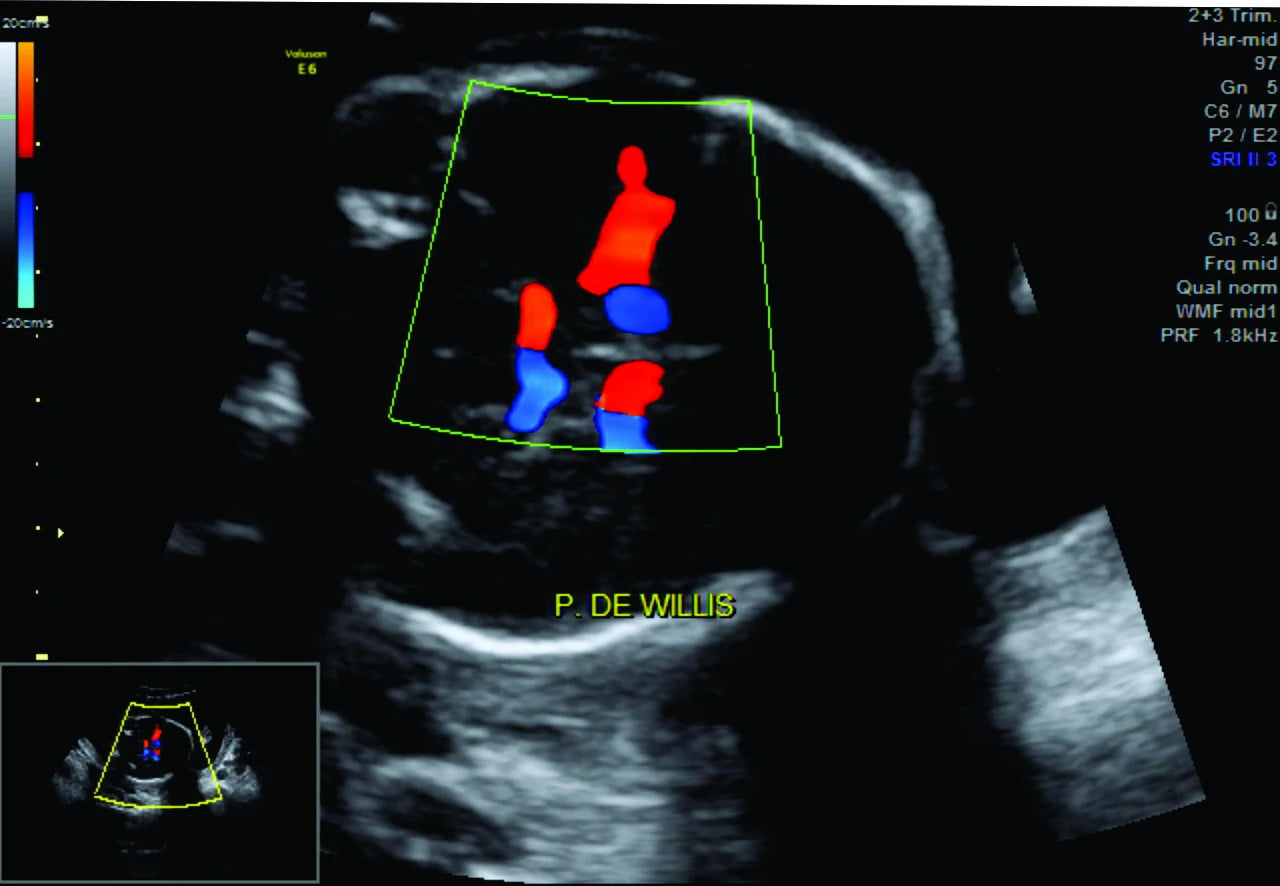

El perfil hemodinámico Doppler fetal es un estudio de ultrasonido especializado que utiliza la tecnología Doppler para evaluar la circulación sanguínea en el bebé y la placenta. Este examen permite a los médicos detectar posibles problemas de flujo sanguíneo y asegurar que el bebé reciba suficiente oxígeno y nutrientes a través de la placenta. Es una herramienta valiosa para monitorear el desarrollo y bienestar fetal, especialmente en embarazos de alto riesgo.

Imagen: Imagen de un perfil hemodinámico Doppler fetal mostrando la circulación sanguínea en el cordón umbilical y la placenta.